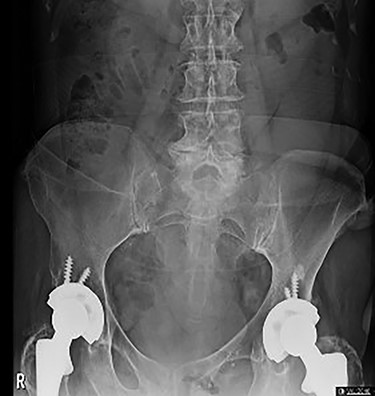

On initial presentation, her blood results were as follows: white cell count (WCC) 14.8 × 109 cells/l (RR 4.3–11.2 cells/l), neutrophils 12.3 × 109 cells/l (RR 2.1–7.4 cells/l) and C-reactive protein (CRP) 1.9 mg/l (RR 0–5 mg/l). Imaging performed included an abdominal film, which showed nonspecific bowel gas pattern (Fig. 1). The patient was managed conservatively and discharged home. She represented 2 days later with worsening symptoms and blood results of WCC 20.1, neutrophils 18.4 and CRP 6. She was admitted under the surgical team and a thoracic and abdominal CT scan was done (Figs 2–4). It was initially reported as significant dilated small bowel loops in keeping with small bowel obstruction due to a femoral hernia. However, the scan was revisited by the surgical team in more detail as the images appeared to represent an obturator hernia. Upon further discussion, these findings were corroborated by the radiologist and a strangulated left obturator hernia was identified.

Distended stomach and dilated bowel loops with an obturator hernia (pointed by the arrow), as shown in the coronal section.